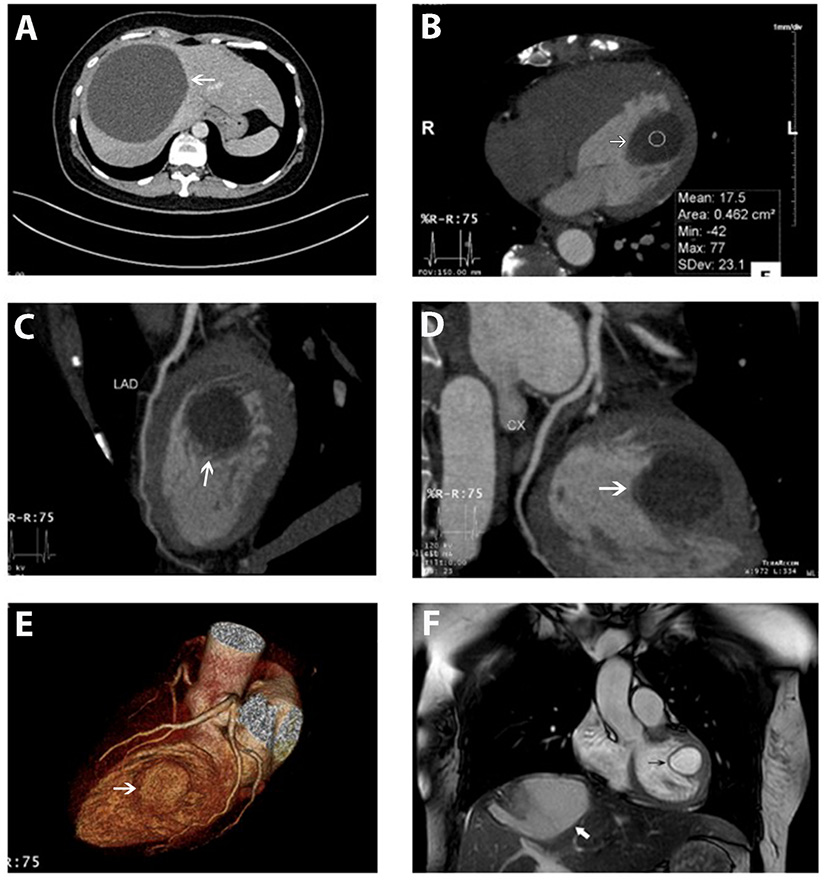

On cardiac CT images, the lesion looked primarily intracavitary. Contrast-enhanced MDCT of the heart showed an encapsulated, rounded and fluid-attenuated, non-calcified structure along the LV lateral wall measuring 32 mm × 24 mm, its morphologic features looked similar to that of the hepatic cyst which was shown in the Figure 2A. There was no enhancement seen following IV contrast. Coronary MDCT excluded coronary stenosis; coronary aneurysm, which may have mimicked some of the findings on echo; and coronary compression caused by the cyst. In computed tomographic 3D volume-rendered images, the cyst was also clearly seen not in contact with coronary arteries (Figures 2B–E).

Figure 2

Hepatic cyst and the cardiac cyst on CT and on MRI. (A) A giant hepatic cyst was seen on the abdominal CT scanner (white arrow). (B–E) An encapsulated, rounded, and fluid-attenuated non-calcified structure along the LV lateral wall (white arrow) and its spatial relationship with coronary arteries (left anterior descending, circumflex) on MDCT. (F) Cardiac cyst (black arrow) and the hepatic cyst (white arrow) were simultaneously depicted on MRI. The cardiac cyst was a single intramuscular cyst located at the anterolateral papillary muscle attached to the LV lateral free wall, protruding into the LV cavity, not enhanced by the gadolinium. Myocardial perfusion and enhancement were normal.

Cardiac MRI also demonstrated a single intramuscular cystic mass located at the anterolateral papillary muscle attaching to LV lateral free wall and protruding into the ventricular cavity (Figure 2F and Supplementary Video 4). The cyst was not enhanced by gadolinium and was measured at 24 × 23 × 30 mm. Myocardial perfusion and enhancement were normal. LVEF and cardiac indexes were 77% and 2.8 l/min/m2, respectively. The flow void on CMR confirmed the normal activity of the cardiac valves without intracardiac obstruction.